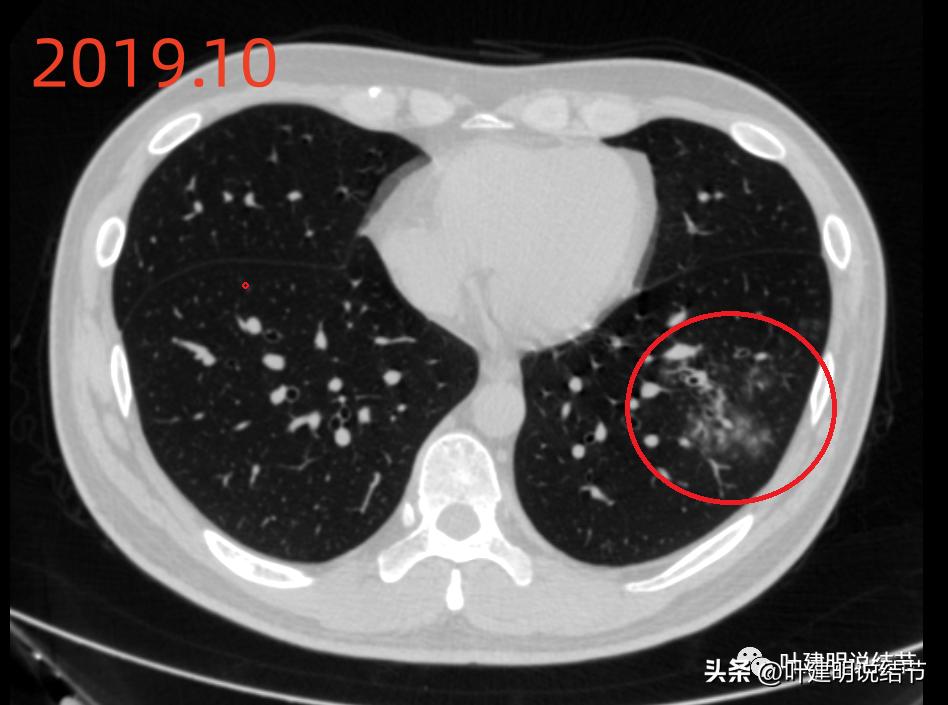

当时左下有肺炎。

上图也是当时左下的炎性区域。

先看2022年6月的片子时,感觉左下叶红色圈起来的像原位癌,桔色圈起来的像不典型增生可能性大些。但回顾2019年的片子,当时有肺炎,如绿色圈起来的范围内都是炎症性的,那时候这两个病灶也有,但红色这处当时瘤肺边界模糊点,桔色这处密度比现在感觉要高点,又结合当时炎症过,所以总体看来,桔色的考虑慢性炎性结节可能性大;红色的虽不能除外原位癌,但也无法除外炎性,至少风险应该不算高,如果再随访下也可以的。若手术,红色的要后基底段切除,桔色的要前内基底段切除,就留下外基底段与背段感觉有些孤立;若均楔形切除也是可以的,但若均是炎性,则不划算,我个人意思仍是风险不大情况下,再观察下,反正危险不大嘛!